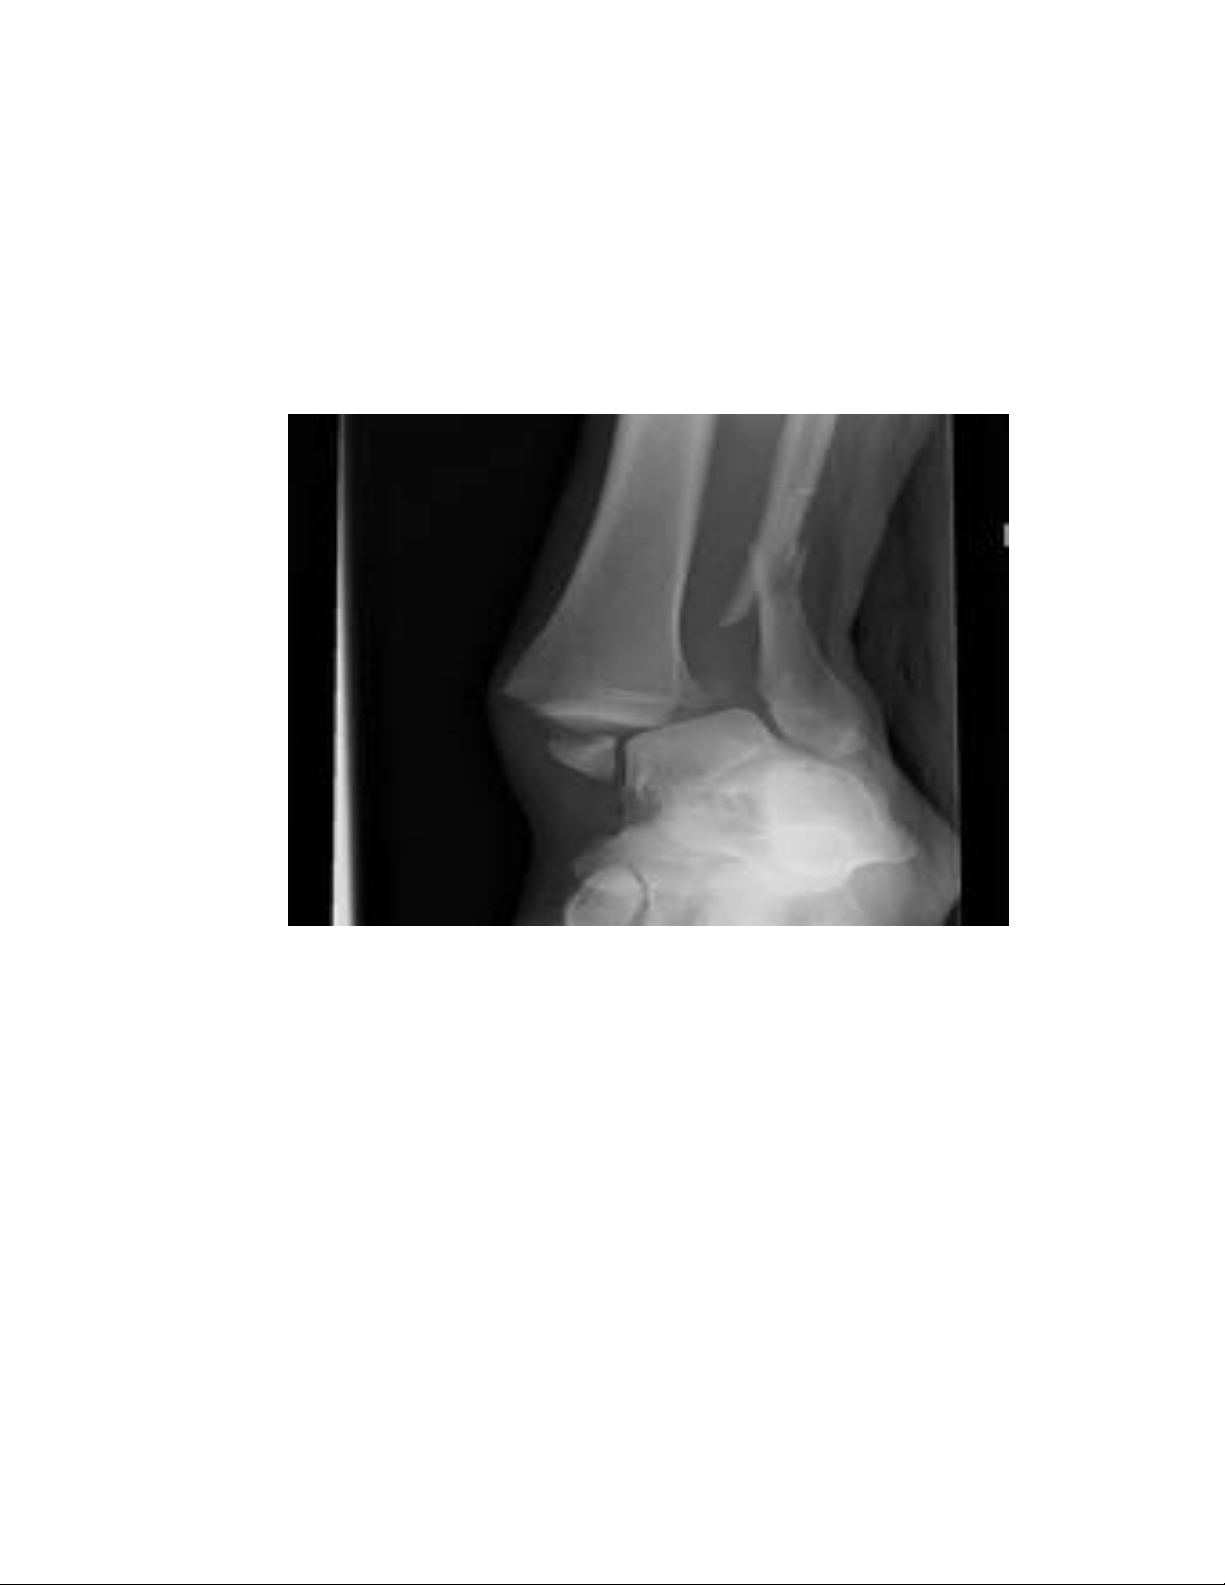

quá lớn, bị chấn thương kéo dài. Dần dần mọc gai xương gót, có thể làm tổn

thương vùng gót chân bị tăng lên đáng kể. Mũi bàn chân là một phần phải chịu lực

thứ hai sau cổ chân, lại bị bó hẹp do mũi giày nhọn ở đầu. Phần mũi bàn chân, đến

lượt mình cũng phải hứng chịu phần đáng kể trọng lượng cơ thể, dẫn đến tình

trạng thoái hóa sớm các khớp bàn chân, ngón chân và biến dạng khớp, đặc biệt là

ngón chân cái bị trẹo ra ngoài, còn các ngón chân khác cũng bị biến dạng, thoái

hóa ở các mức độ khác nhau. Bàn chân sưng phù do máu dồn về đôi chân gây cảm

giác đau đớn, khó chịu. Như vậy đi giày cao gót có thể gây phù, đau và biến dạng

bàn chân, lỏng lẻo khớp cổ chân hay khớp cổ chân bị thoái hóa sớm, mọc gai

xương gót. Mức độ tổn thương đôi chân phụ thuộc vào loại giày cao gót cũng như